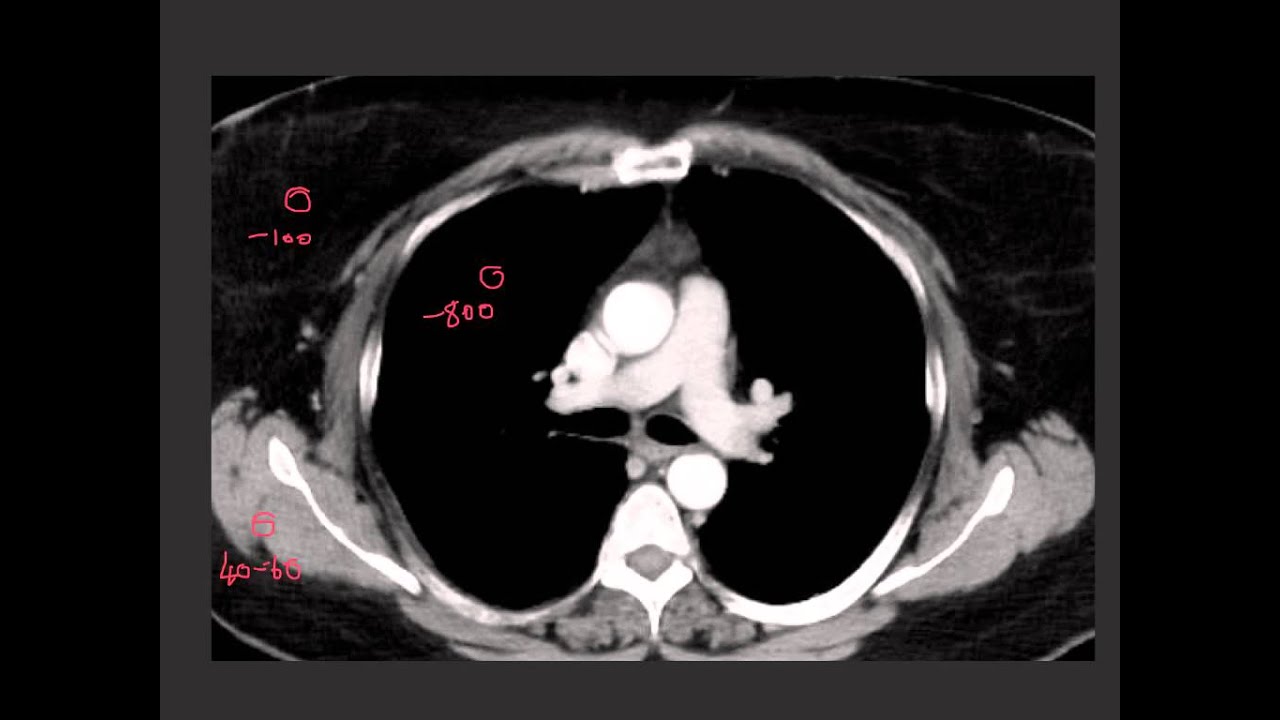

hi this is Pam Johnson with today's resident presentation on gated chest CT pearls and pitfalls so when do we use a gated acquisition well the role of a gated acquisition is to minimize cardiac motion and gating can be performed retrospectively or prospectively because the motion artifact from the beating heart can cause all kinds of artifacts that mimic pathology and also limit the quality of the study particularly in coronary artery imaging in aortic valve evaluation we have to image with gating so that we maximize our temporal resolution and decrease the motion artifacts that limit image quality

so let's look at this unguided study on a young woman who came in with chest pain and has what looks like a small dissection in the a semi thoracic aorta now we have all seen the pulsation artifact that looks like a dissection and in this case very well could be a pulsation artifact but she had a very strong clinical suspicion for dissection and we couldn't be absolutely sure that this wasn't a dissection so she was imaged the following day with a gated study look at the difference the case on the right there is no artifact